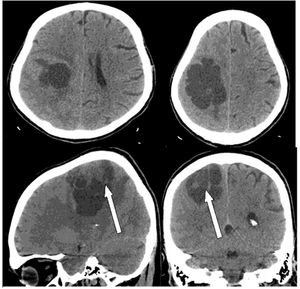

Case History: A 65-year-old patient presented with complaint of sudden onset of left sided hemiparesis.